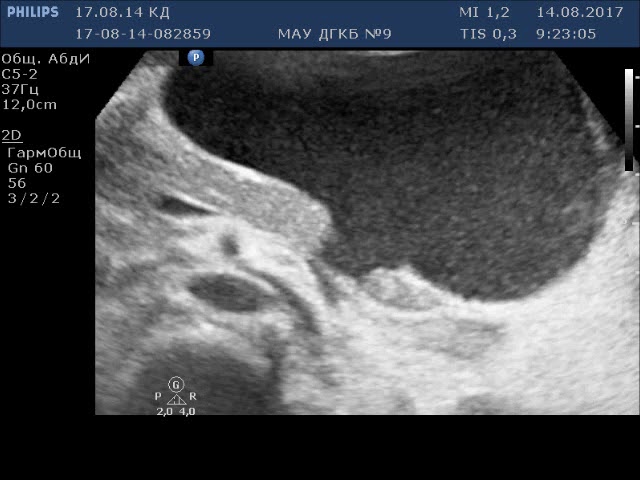

В спорных случаях проводится функциональная диагностика: УЗИ, лапароскопия, ангиография, пункция брюшной полости, при которой обнаруживается кровь. Но в условиях прогрессирующего ухудшения состояния проведение их маловероятно.

К прямым признакам относятся увеличение размеров, отек ПЖ, разрыв (в том числе полный поперечный разрыв), гематома в паренхиме, неоднородное контрастирование.